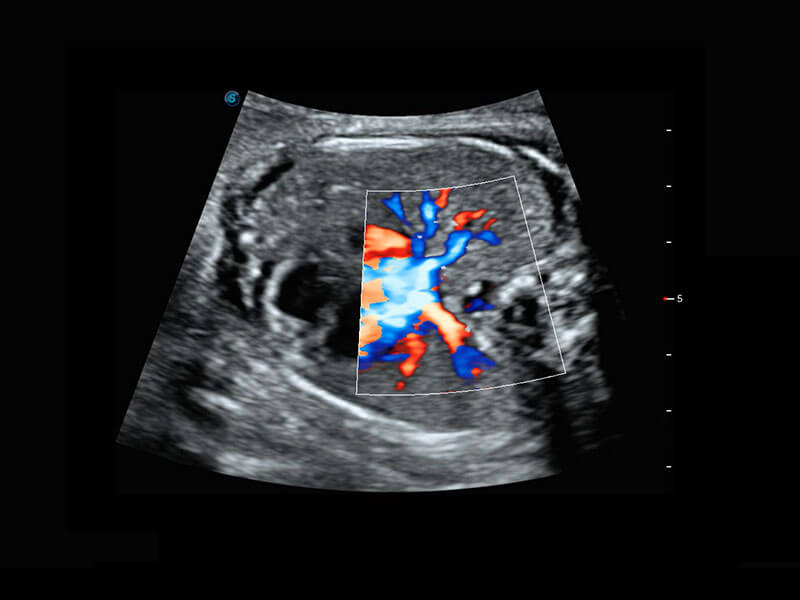

P60在胎儿早孕期超声筛查中为您带来优异的图像质量。

早孕-胎心

高分辨率容积成像-早孕胎儿

胎儿体循环

光影成像-孕囊